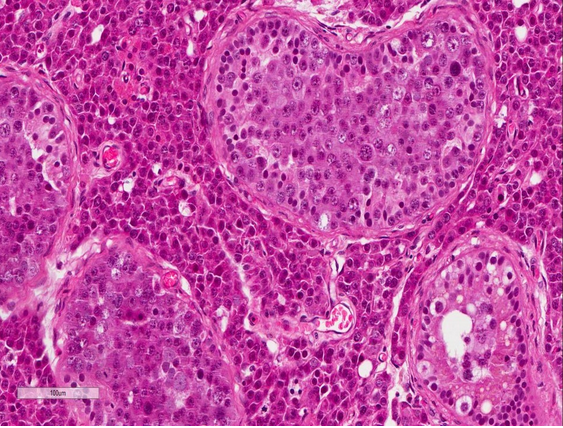

From testicular mass.

Histo features?

Dx?

Seminoma

Histo: Large cells with clear cytoplasm and squared off nuclei and prominent nucleoli admixed with inflammatory cells (lymphocytes and plasma cells in fibrous bands)